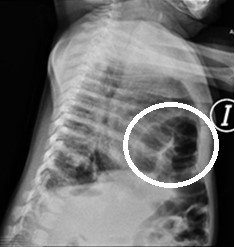

Paciente de sexo femenino de 5 meses con diagnóstico de Trisomía 21. Ecocardiograma control evidencia hernia diafragmática, se solicitan radiografías de tórax diagnosticando Hernia de Morgagni (HM).